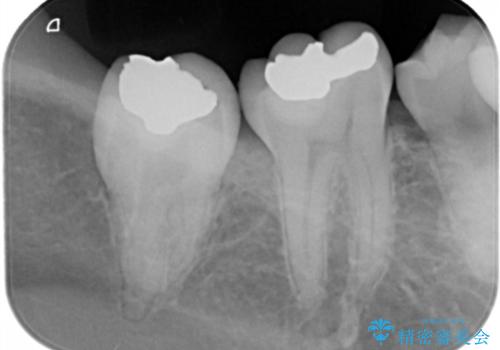

奥歯の深い虫歯

- 以前他院で奥歯にプラスチックの樹脂で虫歯治療を行った患者様です。

かかりつけの歯科医院で虫歯だと指摘され、自費でのゴールドインレーでの修復治療を希望して来院されました。

古い樹脂の詰め物を取り除いたところ、歯の神経と非常に近い状態でした。

万一神経と交通した場合に備え、唾液が入らないようにゴムのシートで防湿(ラバーダム防湿)を行い虫歯除去を行いました。

幸い神経とは交通せず、処置後の神経症状もありませんでした。